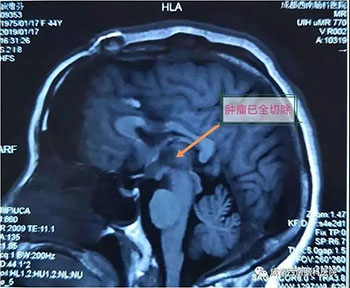

中脑海绵状血管瘤手术

术前

术后